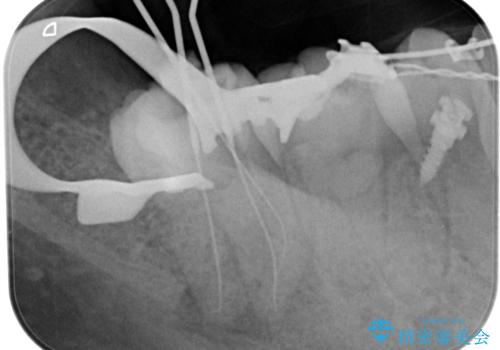

治療中、細菌の除去を徹底的に行えるように顕微鏡とラバーダム(ゴムのシート)を用いて行いました。

できるだけ来院回数を減らすことができるように1回の予約は90分ぐらいで集中して治療していきます。

治療中の写真は患者様にお見せしますのでより安心して治療を受けていただけたと思います。